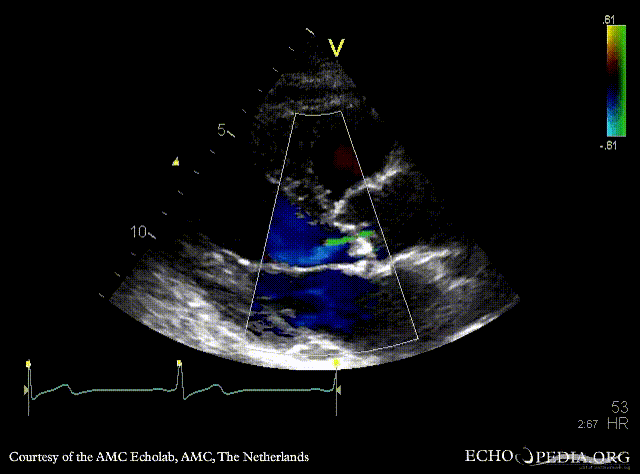

E00864.jpg

E00865.jpg

Continuous-wave Doppler signal of transaortic flow Pulsed-wave Doppler signal of flow in left ventricle outflow tract